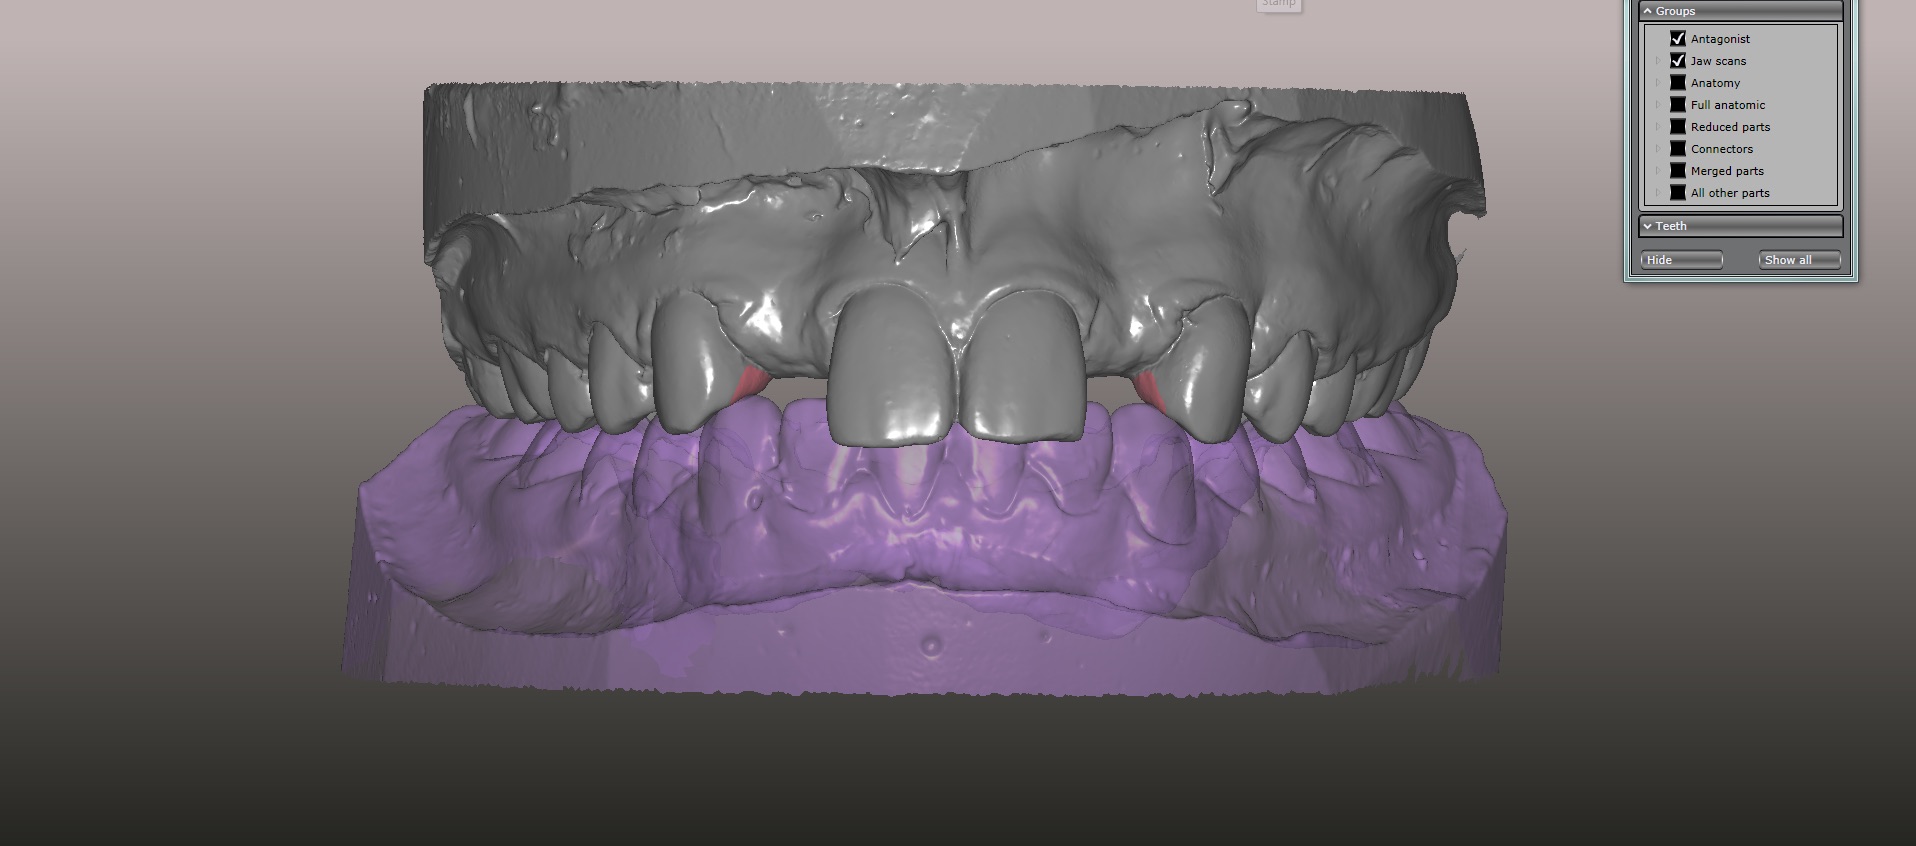

(15.) Models mounted in maximum intensity projection, allowing design of the retainer extensions on the lingual of the canines (in pink).

Figure 15

An approach utilizing CAD/CAM was employed to fabricate an accurate fitting, retentive, and esthetic ceramic single-wing resin-bonded bridge. Impressions were taken of the patient and scanned in the laboratory using maximum intensity projection. The scanned models were then used to design the final prosthetic frames utilizing EXOCAD software. The retainer positions and extensions were designed on the models based on the occlusal clearance (Figure 15). Next, the replacement tooth forms were chosen from a virtual library (Figure 16), and try-in PMMA bridge prototypes were milled in Primotec USA PMMA. This allowed for try-in of the design, adjustment of the contacts, and intraoral evaluation of the ridge contact (Figure 17). Once tried and idealized for both fit and occlusion, the design was sent back to the lab to rescan. Utilizing the software, a cut back was made on the lateral incisor (Figure 18), and a 0.3mm space was also virtually designed on the internal surface of the retainer wing to allow layering with feldspathic ceramic (Figure 19). The 0.2 mm internal edge of the wing was designed to be left intact to allow for precise seating and verification of fit on the model. After the frame was milled in zirconia (Zirconzahn, Prettau), it was verified on the model, and high fusing margin porcelain (Noritake CZR) was mixed with a clear utility wax and applied to the internal 0.3 mm depression. This was baked in the oven at a high temperature, allowing the wax to burn out and leaving the feldspathic ceramic fused to the internal surface of the retainer. Once cooled, this was checked for precise fitting on the model and adjustments were made to ensure full seating.